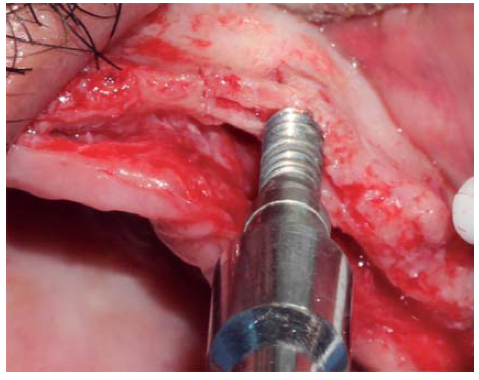

A full thickness incision over the crest was performed, raising a mucoperiosteal flap exposing bone table up to 4 mm from the top of the crest in vestibular direction; from that point the flap was divided into partial thickness (Figure 3). After this, impact points were marked in designated places according to surgical guide for implant placement; perforations were initiated with a 1.6 mm diameter burr in order to determine desired implant depth and axis. After this, a ridge was created on the crest with a diamond burr, fracturing cortical bone to create chisel's access to cancellous bone, and with the aforementioned, bone tables were separated until reaching a 5 mm depth (Figures 4 y 5). Perforations were further continued with a 2.0 diameter burr (Figure 6), and vestibular table expansion was undertaken creating greenstick fracture with the expanders, until reaching sufficient osseous bed diameter (3.2 mm diameter) (Figures 7 y 8). Implants were then placed at a 25 rpm speed and 35 Nem torque (Figures 9 y 10). After this, a particulate bovine bone graft was placed (Bonefill® Bionnovation Biomedical, Sao Paulo, Brazil) with the aim of preserving integrity of vestibular bone tables (Figure 11). All these procedures were repeated for placement of all six implants. Finally, sutures were undertaken with monofilament nylon 5/0.

Figure 5 Bone chisel entering medullar portion, separating cortical ridge leading to greenstick fracture.